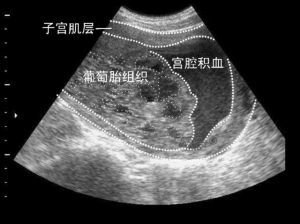

请到家中才了解到,他的颓丧来源于怀孕妻子被检查有宫腔积血,大多人在听到这个名词的时候,脑海中会浮现出一些血淋淋的场景,第一反应就是好严重,怎么办?怎么办?

其实,西柚医生在临床工作中也会碰到早孕期宫腔内有积液的病症,有些孕妇可以从怀孕开始一直维持到妊娠晚期,大小从1厘米到7-8厘米不等,而这些积液大多数是积血。